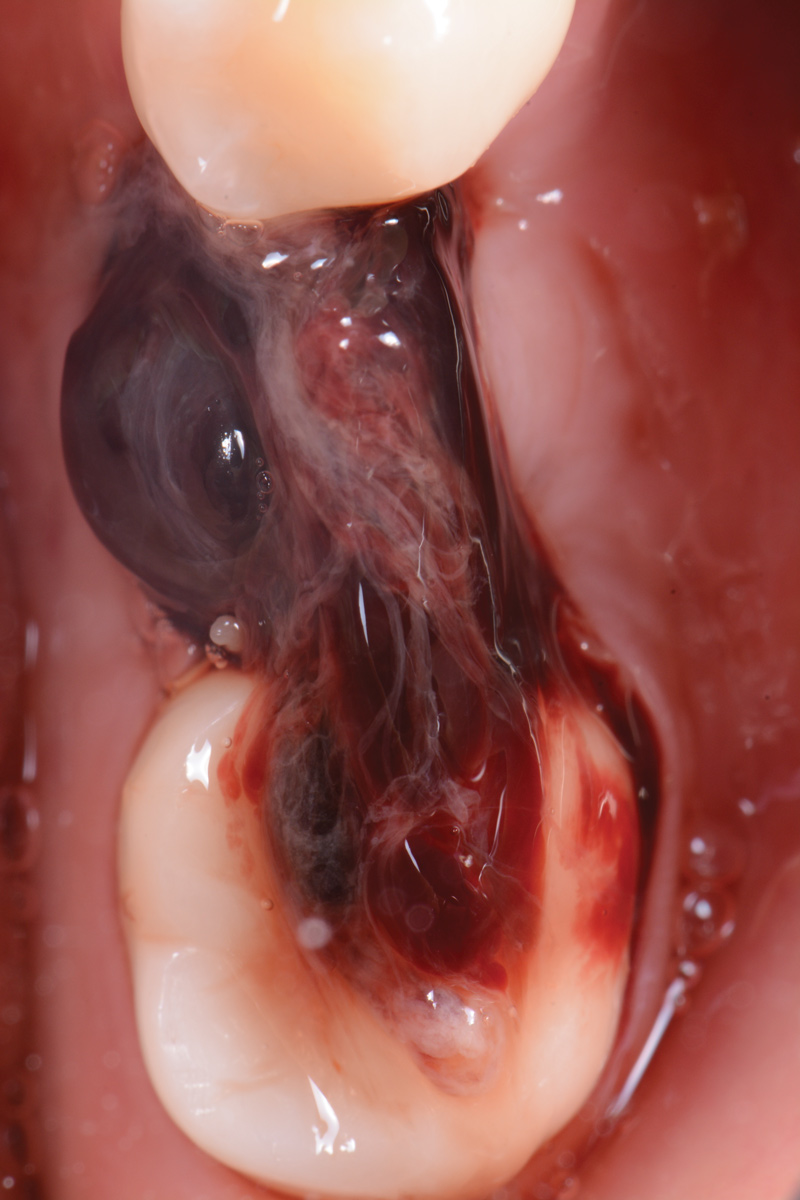

Three months later, the patient was scheduled for second-stage surgery to place a healing abutment. When asked, the patient stated that she had no changes in her medical history. Following local anesthesia infiltration, a crestal incision was made and a full-thickness flap was elevated in the No. 19 area to expose the implant cover screw. A healing abutment measuring 5 mm x 5 mm was placed, and two single interrupted resorbable sutures were used to close the flap.

Fig 1. Second-stage surgery.

Figure 1